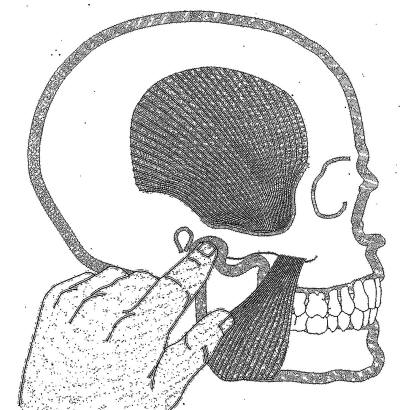

Palpación del músculo temporal |

El temporal también no presenta inconvenientes a la

palpación, dado que es un músculo menos poderoso que el

masetero, solemos pedirle al paciente que apriete sus

dientes co intervalos de descanso, para obtener respuesta

dolorosa a la palpación. |